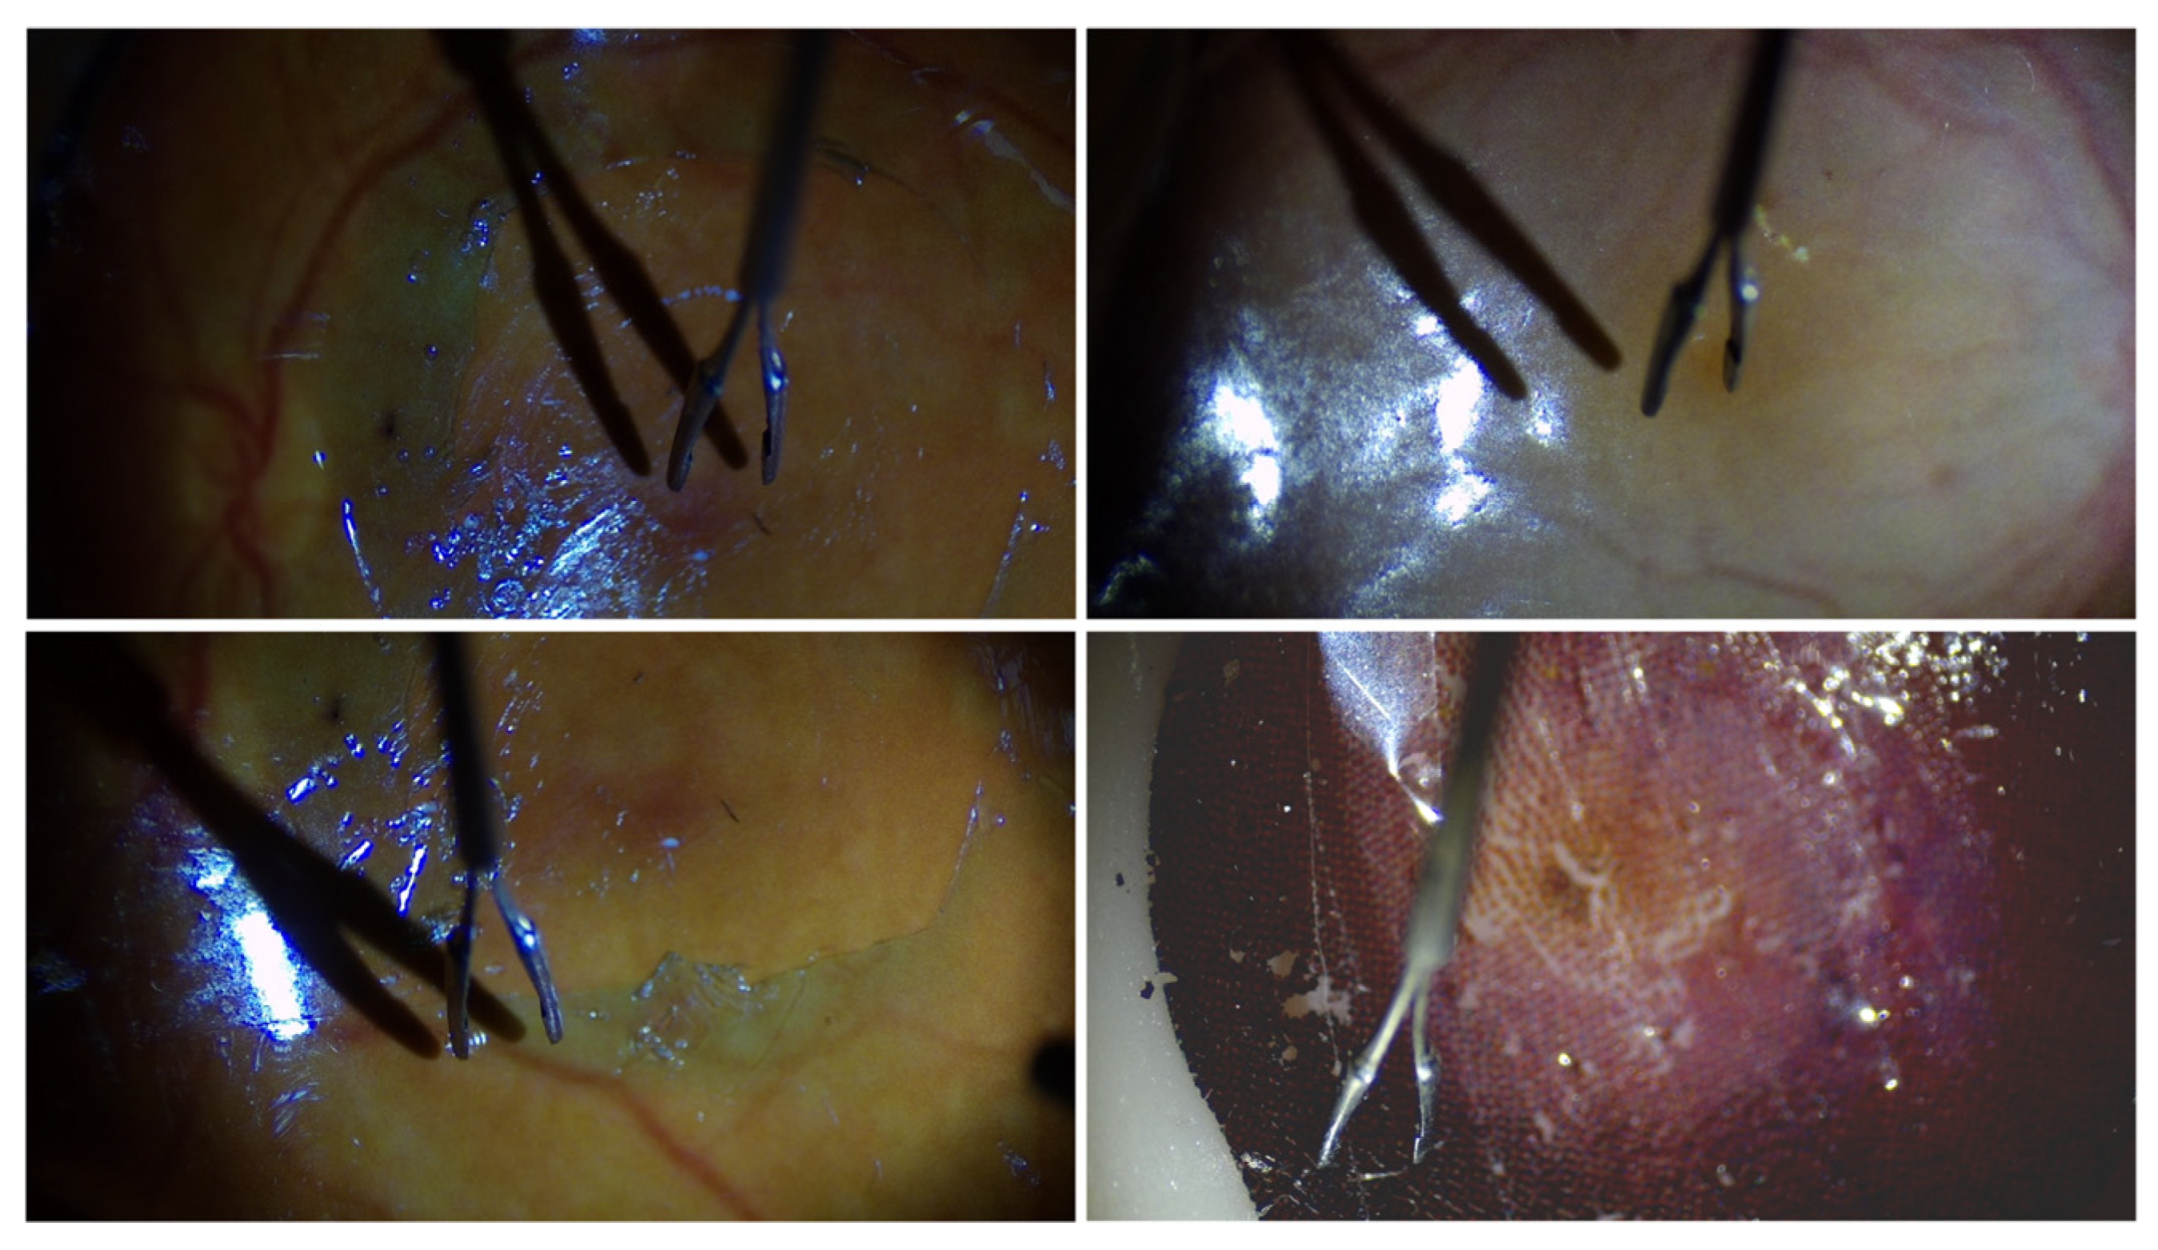

4.3. Break Initiation Experiment in ILM Peeling